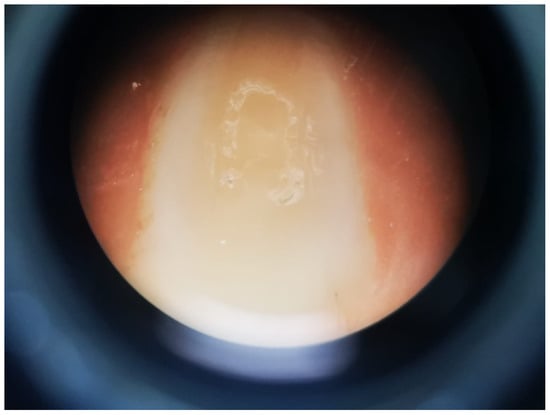

2.4. Contact Angle

3.2. Contact Angle